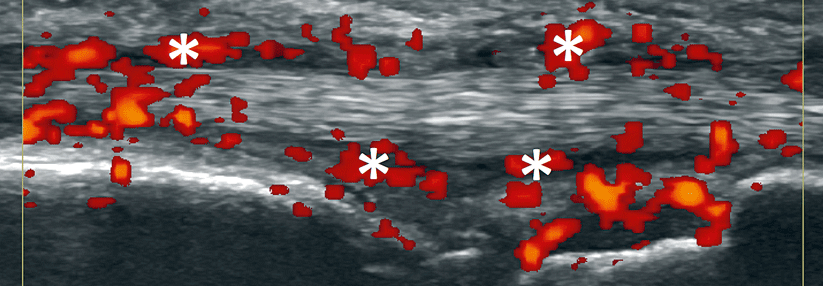

Wenn Patienten mit rheumatoider Arthritis gut auf TNF-Blocker ansprechen, stellt sich die Frage, ob man diese auch wieder absetzen kann. Einer aktuellen Studie zufolge ist dies oft möglich, ohne die Remission zu gefährden.

Arbeiten zur Beendigung einer einmal begonnenen antirheumatischen Therapie bei anhaltender Besserung gibt es bisher wenig. In der OPTIMA*-Studie ist man diesen Weg gegangen: 1032 Patienten mit früher rheumatoider Arthritis erhielten zusätzlich zu Methotrexat (MTX) entweder den TNF-alpha-Blocker Adalimumab oder ein Scheinmedikament. Als Therapieziel galt eine niedrige Krankheitsaktivität, gemessen an 28 Gelenken (DAS28 < 3,2) sowie dem CRP-Wert. Erwartungsgemäß erreichten mit dem Biologikum nach 22 bzw. 26 Wochen deutlich mehr Teilnehmer dieses Ziel (40 vs. 22 %).